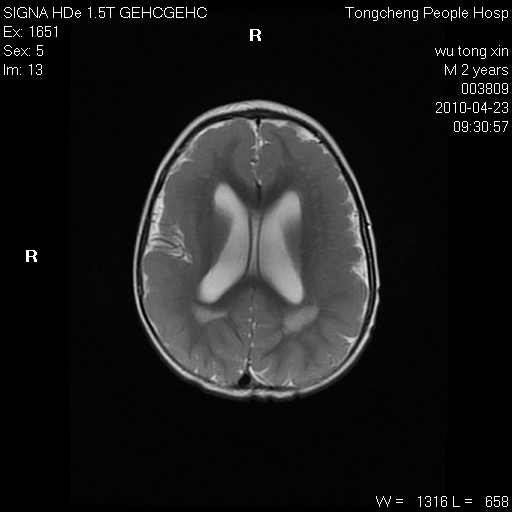

以下是引用赵物学在2010-4-25 12:43:00的发言:[br]巨脑回[br]侧脑室后角低密度影考虑hie或肾上腺脑白质营养不良?[br][br][本贴已被 赵物学 于 2010-4-25 12:51:28 修改过]

以下是引用gaoxiao在2010-4-25 16:54:00的发言:[br]巨脑回畸形。脑白质髓鞘化不良

以下是引用pujunzhi在2010-4-25 21:35:00的发言:[br]考虑 1双侧大脑皮质发育不良 2轻度脑积水 3双侧脑室后角旁片状长t1长t2信号,需继续观察,因为正常小儿此处脑白质的髓鞘化时间可以延迟到4-6岁,才显示正常。